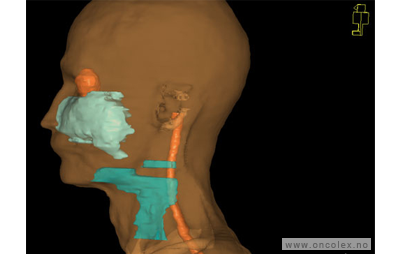

Skisse over hvordan strålefeltet planlegges:

Illustrasjon for målvolum

• GTV (Gross Tumor Volume): Identifisert tumor.

• CTV (Clinical Target Volume) GTV + omkringliggende vev hvor det kan væremikroskopisk spredning.

• ITV (Internal Target Volume): CTV + en indre margin som tar hensyn tilindre bevegelser og endringer av CTV.

• PTV (Planning Target Volume): Innstillingsmargin som inneholder ITV og samtidig tar hensyn til antatte pasientbevegelser, samt variasjoner i pasientopplegging og feltinnstillinger.

• Feltgrense. Tegnes som oftest på kroppen.

ICRU (International Commission on Radiation Units and Measurements)